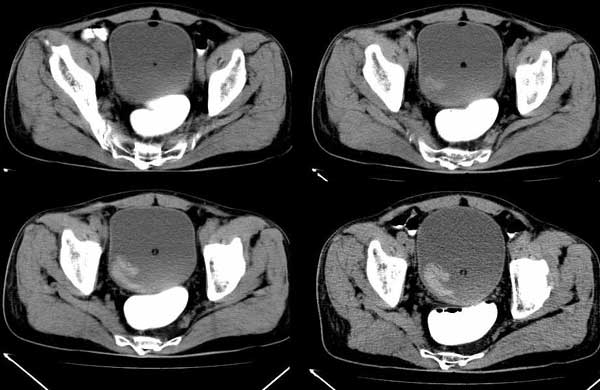

m/76 患者于2个多月前无明显诱因出现解肉眼血尿,为淡暗红色,无尿急、尿痛、脓尿,自服中草药后症状缓解

膀胱内高密度ct值约62hu

膀胱内偏右后方附壁见不规则软组织密度块影,边缘有分叶,综合患者症状考虑膀胱癌。

本人首先考虑膀胱内血凝块!跟踪临床经膀胱镜检查证实,但另有发现:膀胱冲洗血凝块后发现右侧壁见菜花样物质。

患者行膀胱镜检查,将血块冲洗后发现有菜花样物质! 当时完全被血块掩盖了!

今天下午病理出来了,是膀胱移行细胞癌